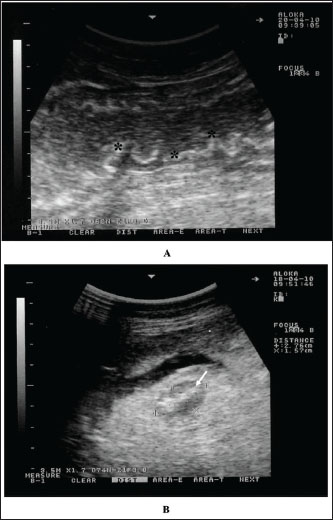

Ultrasonography has been confirmed as a safe, very beneficial for diagnosis of several diseases and disorders of the gastrointestinal tract in dromedary camels (Tharwat et al., 2012a,b,c; Tharwat et al., 2013; Tharwat and Al-Sobayil, 2016; Tharwat et al., 2018; Tharwat, 2019; Tharwat, 2020; Sadan et al., 2024; Tharwat, 2024; Tharwat et al., 2024b,c,d,e; Tharwat and Tsuka, 2024). As a rapid screening test for dromedary camels with suspicion to be affected with PTB, clinicians may use sonography to image the abdominal viscera, especially the intestines and mesenteric lymph nodes (LNs) (Tharwat et al., 2012a). Usually, the intestinal wall becomes either mildly, moderately, or severely thickened (6.8 ± 1.9 mm; 12.8 ± 4.6 mm, and 17.5 ± 3.6 mm, respectively) versus a thickness of 3.6 ± 1.2 mm in healthy non-affected camels. Visualizing of enlarged mesenteric LNs was also reported (Tharwat et al., 2012a). The LN capsule was either anechoic or echoic, and the contents were either echogenic, anechoic, or heterogenous. Other sonographic findings include bright hepatic parenchyma, aggregation of echogenic materials separated with fluids among the intestines, and pleural and pericardial effusions (Fig. 2) (Tharwat et al., 2012a).

Fig. 2. Intestinal imaging in a dromedary camel with paratuberculosis. The intestinal walls were thickened and corrugated (stars) (A). Image B shows an enlarged mesenteric lymph node (white arrow) having an echogenic core. Scanning was performed at the right ventral abdomen using a 3.5 MH sector transducer.